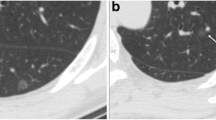

Representative cases of pure ground-glass nodules. a Adenocarcinoma-in-situ in a 42-year-old man. Two-dimensional average diameter was 7.6 mm, and nodule mass was 0.11 g (contrast-enhanced CT). Both measurements corresponded well with the diagnosis. b Adenocarcinoma-in-situ in a 47-year-old man. The two-dimensional average diameter was 13.3 mm, and nodule mass was 0.49 g (non-enhanced CT). Based on the volumetric measurements, invasive adenocarcinoma was more likely than a preinvasive lesion. c Adenocarcinoma in a 45-year-old male. Two-dimensional average diameter was 9.2 mm, and nodule mass was 0.17 g (non-enhanced CT). Volumetric measurements, which are suggestive of a preinvasive lesion, were discordant with the diagnosis. Invasive component size was 6 mm in this lesion